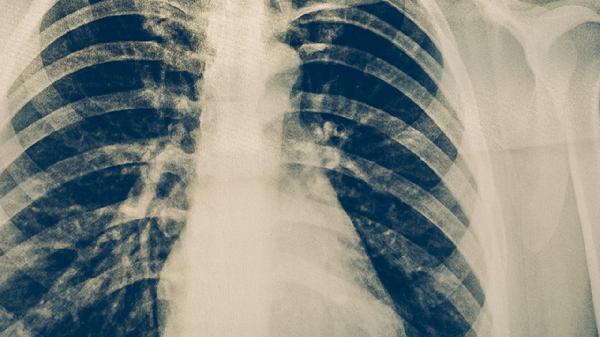

结核病后期多见气阴两虚。生脉饮含人参、麦冬等,适用于乏力、低热等气虚症状。河车大造胶囊含紫河车等血肉有情之品,能改善病后体虚。体质调理需坚持3-6个月,期间定期复查胸片评估病情变化。

肺结核患者服用中药期间需严格遵医嘱,不可替代规范抗结核治疗。建议保持高蛋白饮食如鸡蛋、鱼肉,适量补充维生素A、D。避免辛辣刺激食物,戒烟限酒。保证每日8小时睡眠,进行散步等温和运动。每2个月复查胸部CT和痰培养,监测肝肾功能。出现皮疹、黄疸等不良反应时立即就医。